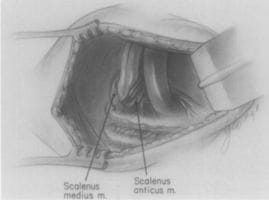

Adson and Coffey at the Mayo Clinic suggest the mechanism by which the anterior scalene muscle causes neurovascular compression in patients with cervical ribs, and are the first to demonstrate that scalenotomy alone can relieve the symptoms of neurovascular compression, without resection of the cervical rib. This procedure becomes popular for several decades, although the recurrence rate is very high. Dr. Alfred Washington Adson created and headed the Section of Neurological Surgery at the Mayo Clinic. He was a pioneer in American surgery, was a founding member and president of the Society of Neurological Surgeons, and was president of the Minnesota State Medical Association and the Minnesota State Board of Medical Examiners.. Dr. Alfred Washington Adson created and headed the Section of Neurological Surgery at the Mayo Clinic. He was a pioneer in American surgery, was a founding member of the Society of Neurological Surgeons, and was president of the Society of Neurological Surgeons, of the Minnesota State Medical Association, and the Minnesota State Board of Medical Examiners. In 1938, Adson performed the first total anterior scalenectomy, removing the entire muscle.

Naffziger and Grant first introduce the concept of neurovascular compression in the thoracic outlet due to scalene muscle anomalies, without the presence of a cervical rib. They perform the first scalenotomies in patients without cervical ribs, but do not publish their findings until 1937 and 1938. Dr. Howard Christian Naffziger, who trained under eminent surgeons William Halsted and Harvey Cushing, became one of the most esteemed neurosurgeons of his time. He created the division of Neurosurgery and served as Chairman of the Department of Surgery at the University of California San Francisco, was elected president of the American College of Surgeons, and was Chairman of the committee that established the American Board of Neurological Surgeons. Francis Clark Grant trained under eminent neurosurgeons Charles Frazier and Harvey Cushing. Dr. Grant succeeded Dr. Frazier as Professor and Chairman of Neurosurgery at the School of Medicine and the University Hospital at University of Pennsylvania. He published over 200 papers in his lifetime, and refined or developed several neurosurgical procedures and instruments.

Renowned surgeons Alton Ochsner, Mims Gage and Michael DeBakey at LSU publish a comprehensive study of patients with symptoms of neurovascular compression in the thoracic outlet in the absence of a cervical rib, for which they coin the term, “Scalenus Anticus Syndrome”. They credit Naffziger with first recognizing this mechanism in 1929 in patients without cervical ribs, and suggest the term “Naffziger Syndrome”. Dr. Alton Ochsner was named Chairman of Surgery at Tulane Medical School at the young age of 31, and founded the world-famous Ochsner clinic at Charity Hospital in New Orleans, which remains one of the pre-eminent surgical teaching programs in the country. Dr. Ochsner was the first to report the link between cigarette smoking and lung cancer, and he trained some of the most prominent surgeons of the time, including Dr. Michael DeBakey. Dr. Michael DeBakey is one of the most renowned cardiovascular surgeons in the world. After volunteering for military service in World War II, Dr. DeBakey created the concept of the Mobile Army Surgical Hospital (M*A*S*H unit) that enjoyed stellar success during the Korean War. Dr. DeBakey was one of the first cardiothoracic surgeons to perform coronary bypass surgery, was the first man to perform carotid endarterectomy, and made numerous other contributions to and innovations in cardiovascular surgery, including work on the Dacron artificial graft, the heart-lung machine, and the artificial heart.

Adson performs the first scalenectomy, or resection of the entire anterior scalene muscle. This procedure is then performed intermittently over the next several decades, until Sanders introduces a more refined technique in 1979.